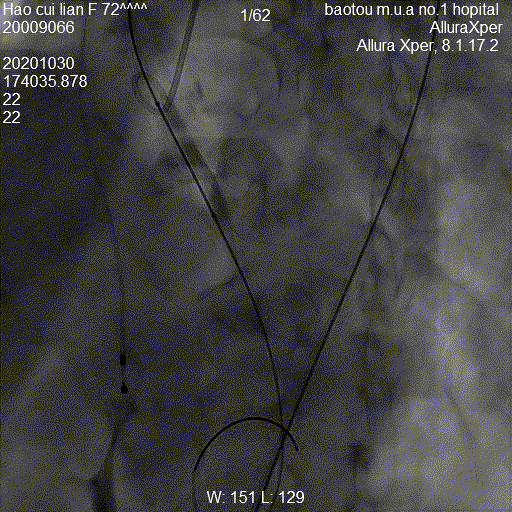

图:手术流程图